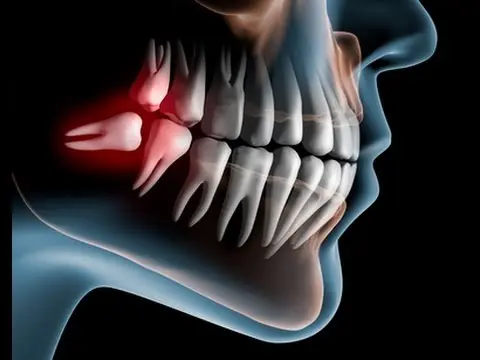

Esta semana hemos conocido una respuesta reveladora, aunque relativa a una estructura distinta: la muela del juicio, esa servidumbre estúpida de la biología humana, ese hueso inservible salvo para la catarsis y el tormento arbitrario, ese contradiós bucodental. El doctor Pangloss, cabe suponer, aduciría que la muela del juicio existe para consolar a los dentistas, y no han faltado biólogos que han encontrado en el último siglo respuestas similares, o similarmente vanas. Mi favorita: que una dieta cada vez más cocinada —tras la invención del fuego— redujo la necesidad del estupendo tercer molar de los homínidos. Pero no del primero y el segundo, parece ser.

La nueva investigación revela un mecanismo mucho más simple y verosímil: que la dentadura se construye siguiendo unos principios generales, leyes geométricas en el fondo, que rara vez están en condiciones de atender a los detalles poco relevantes. La muela del juicio no es un invento genial de Dios, ni de la selección natural darwiniana, para resolver un problema inexistente. Los mismos cambios en la geometría del cráneo que hicieron duplicarse al córtex cerebral —la sede de la mente humana— convirtieron el robusto tercer molar de los homínidos en una rémora para el homo sapiens.